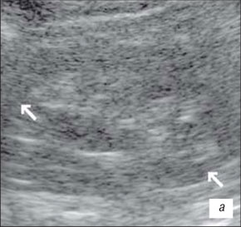

Ехограма розширення порожнинної системи нирки

А – розширення сечоводу:

Б – на тлі сечового міхура.

1 – сечовий міхур, 2 – сечовід

На даній ехограмі спостерігається: зменшення розмірів нирки на стороні поразки; циклічна зміна діаметру сечоводу у верхньому і нижньому відділах; вертикальну спрямованість сечовідно-міхурного викиду, який в нормі має напрям під кутом 30–40° по відношенню до умовної лінії, що сполучає гирла сечоводів.